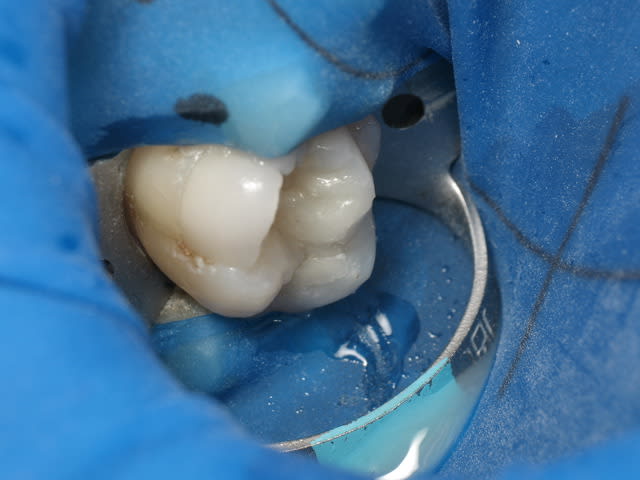

un cas de ce matin.

-avec, IDS (immediate dentin sealing) très pratique pour avoir une étanchéité le jour de la préparation, aurais pu/du se faire sous digue....

- Collage avec composite de stratification chauffé et vibré, très facile pour gérer les excès ...

- Permettra de comparer le vieillissement de l'onlay versus composite direct ...

Oui le compo à été fait le jour du collage, en fait l'amalgame me semblait bien mais aprés dépose de celui sur la 6, j'avais un doute sur une infiltration mésial, j'ai donc déposé le plombage sur 7 le jour de la pose de l'onlay

J'ai monté mon compo en me servant de l'onlay pour modeler la face mésial du composite, puis j'ai collé l'onlay dans un second temps...